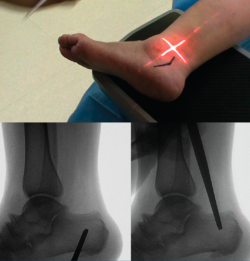

La OPC se realiza bajo anestesia general o regional junto con un bloqueo nervioso anestésico. Se debe tener en cuenta que este procedimiento es tan solo una parte de un conjunto de gestos quirúrgicos destinados a corregir la deformidad, fundamentalmente del pie cavo o pie plano (Figura 1).

Figura 1. Radiografía en carga prequirúrgica.

Se colocan fijaciones púbica y glútea con una almohada entre las extremidades para mantener horizontal la extremidad a intervenir. Se flexiona la rodilla contralateral para que no se vean imágenes fluoroscópicas superpuestas. Se coloca el fluoroscopio a espaldas del paciente (Figura 2).

Se marca sobre la piel la osteotomía propuesta utilizando el fluoroscopio; para ello, es necesaria una imagen lateral del tobillo (se debe visualizar completamente superpuesto el lado medial y lateral de la cúpula astragalina). Para evitar lesiones vasculonerviosas, se ha descrito una zona segura que comprende desde la línea que une la inserción de la fascia plantar con la zona posterosuperior de la tuberosidad del calcáneo y una línea paralela situada 11 mm anterior a la primera(12) (véanse las consideraciones de las complicaciones más adelante).

Figura 3. Se realiza bajo fluoroscopia el diseño de la osteotomía y se marca sobre la piel.

Marcamos el vértice de la V en la piel dentro de la zona de seguridad, desde donde marcamos una línea plantar paralela al borde posteroinferior de la tuberosidad y una linea dorsal paralela al borde posterosuperior de la tuberosidad (Figura 3).